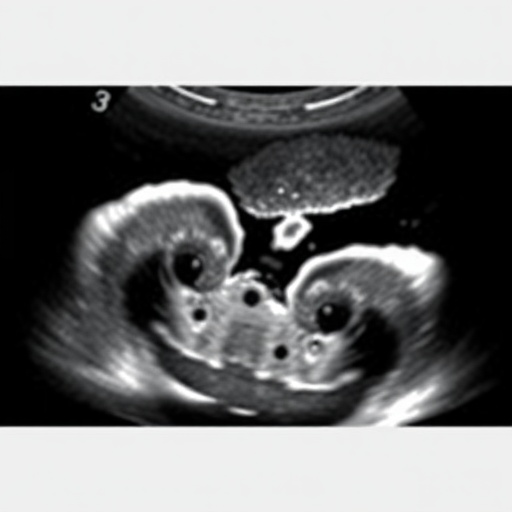

The transcerebellar measurement technique, which involves assessing the size of the cerebellum through ultrasound, has emerged as a reliable indicator of developmental progress. This study highlights its efficacy, noting how the cerebellum’s growth patterns correlate closely with gestational age, providing clinicians with a more objective criterion than traditional methods. Ultrasound imaging is non-invasive and presents no risk to the infant, further enhancing its viability as a standard practice in neonatal care.

In conducting their research, the team employed a retrospective study design, analyzing data from 671 neonates. This method allowed for a comprehensive examination of cases across different gestational age ranges. By comparing the traditional gestational age assessments with those derived from transcerebellar measurements, the researchers aimed to quantify the accuracy of this novel technique. The outcomes reveal that transcerebellar ultrasound can potentially bridge the gap in gestational age determination, particularly where traditional assessments fall short.